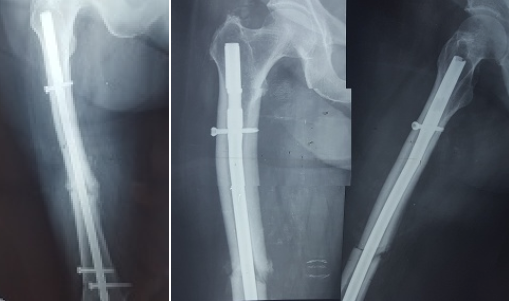

According to the newest guidelines of the ASBMR (American Society of Bone and Mineral Research), the patient underwent intramedullary nailing of the right femur and was instructed to discontinue bisphosphonate along with non-weight bearing of the left lower extremity [17-19]. Although a bone scan was conducted for further investigation of the incomplete fracture and the presence of other imperfect fracture sites, no new lesions were found (Figures 2 and 3). After 6 weeks, there was a clinical improvement in the left femur and radiographic appearance of callus, thus excluding the prophylactic intramedullary nailing of the left femur. The union of both fractures developed normally both for the right femur which was treated with intramedullary nailing and the left femur where conservative treatment was selected. The union of the right femur was not affected by the fact that the distal locking screw was not centered in the nail hole. The radiographic monitoring of the bone healing was conducted at 3, 6 and 12 months after the first treatment took place (Figures 4 and 5).

Figure 4. Postoperative radiographs taken two and six months after surgery. The left one shows one AP view of the femoral shaft with the IM nail. The other two shows one AP and P view of the upper one half of the femur

Figure 5. AP radiograph of both femoral shafts 1-year after surgery